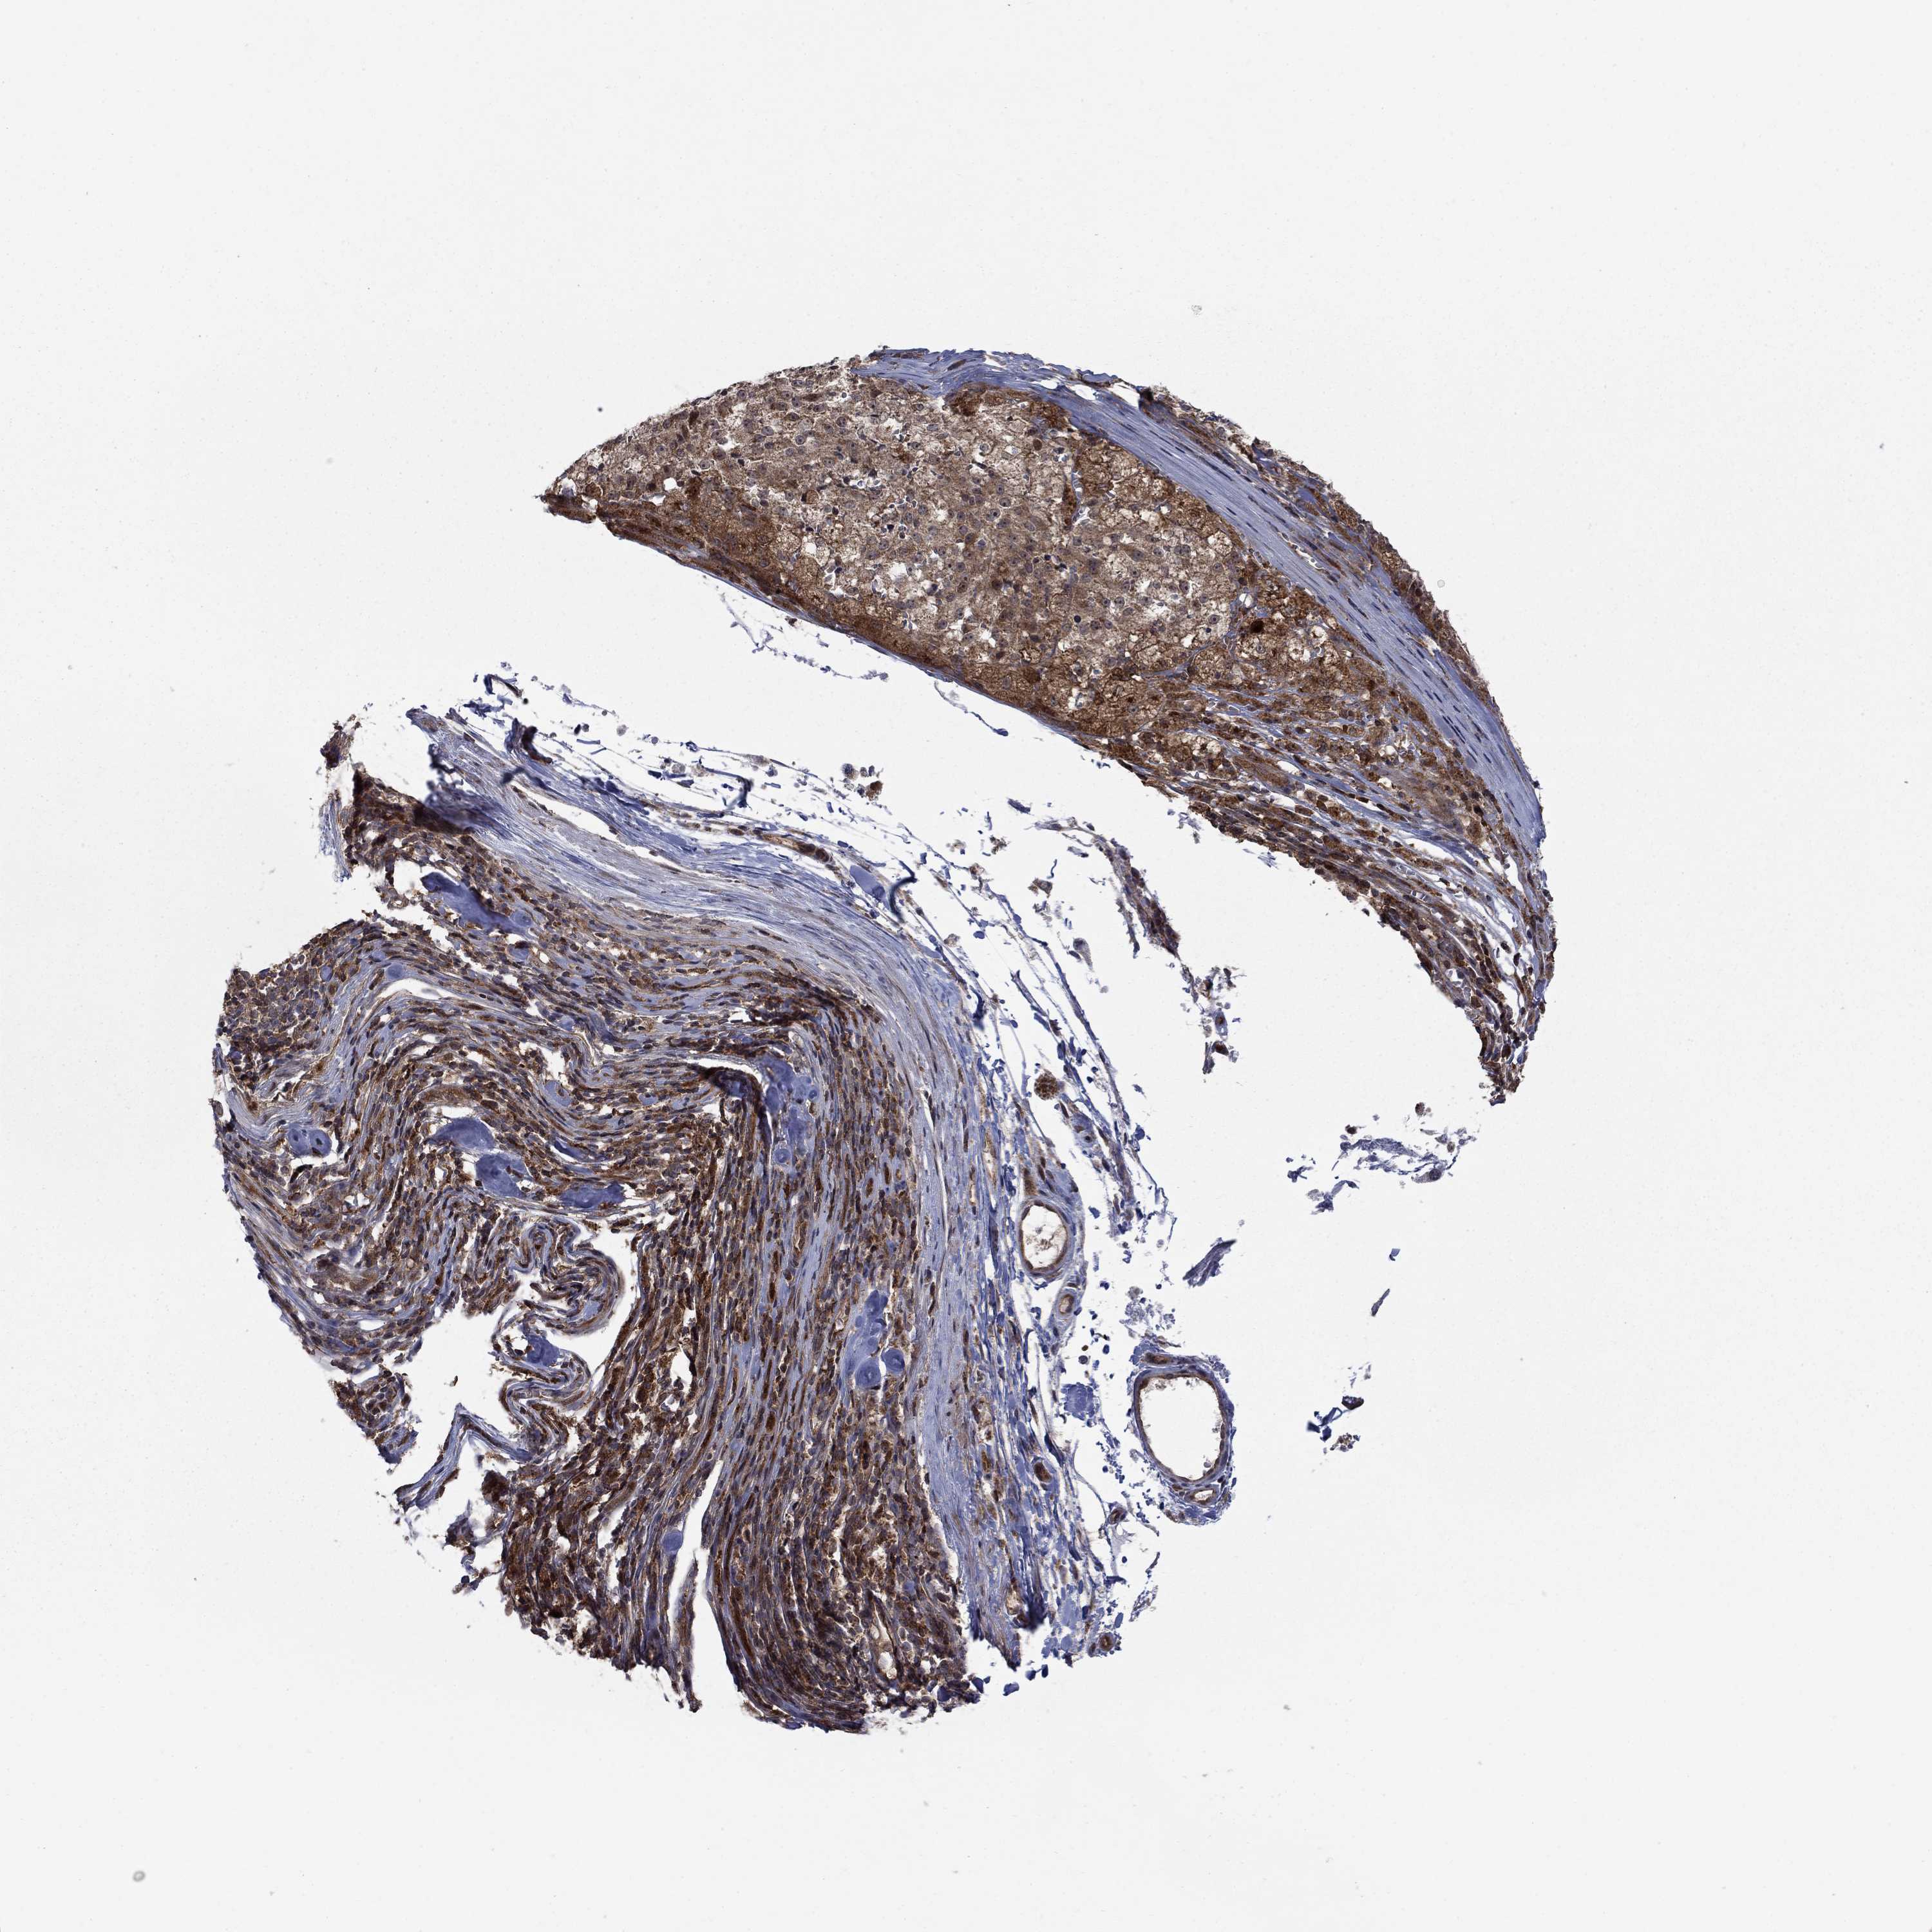

MELANOMA - Protein expressioni

A mouse-over function shows sample information and annotation data. Click on an image to view it in a full screen mode. Samples can be filtered based on level of antibody staining by selecting one or several of the following categories: high, medium, low and not detected. The assay and annotation is described here.

Note that samples used for immunohistochemistry by the Human Protein Atlas do not correspond to samples in the TCGA dataset.

Antibody stainingi

Antibody staining in the annotated cell types in the current human tissue is reported as not detected, low, medium, or high, based on conventional immunohistochemistry profiling in selected tissues. This score is based on the combination of the staining intensity and fraction of stained cells.

Each image is clickable and will lead to virtual microscopy that enables deeper exploration of all samples and also displays staining intensity scores, fraction scores and subcellular localization as well as patient and tissue information for each sample.

Antibody HPA075580

Staining

High

Medium

Low

Not detected

Intensity

Strong

Moderate

Weak

Negative

Quantity

>75%

75%-25%

<25%

None

Location

Nuclear

Cytoplasmic/membranous

Cytoplasmic/membranous,nuclear

Malignant melanoma, NOS

Malignant melanoma, Metastatic site